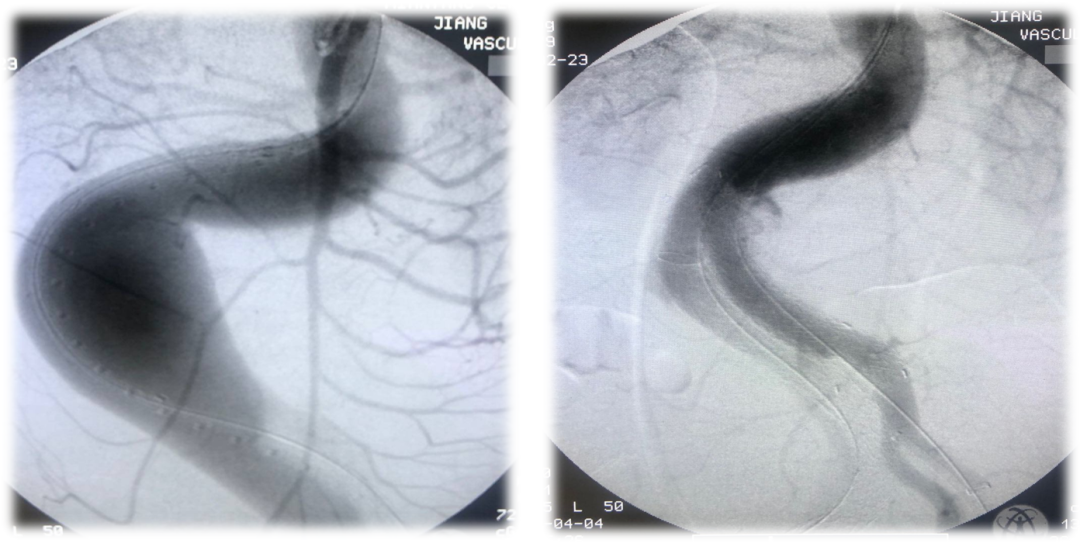

手术过程中,先进行髂内动脉栓塞,再实施腹主动脉EVAR手术。

术后三天出现了严重并发症,患者出现II型内漏,推测主要来源于未彻底封堵的髂内动静脉瘘;同时,患者右侧肢体进行性无力,小腿肌肉瘫痪,肌力降为0级,膝关节、踝关节功能受限,小腿外侧及足部感觉丧失,这是髂内动脉封堵后引发的臀肌缺血症状。